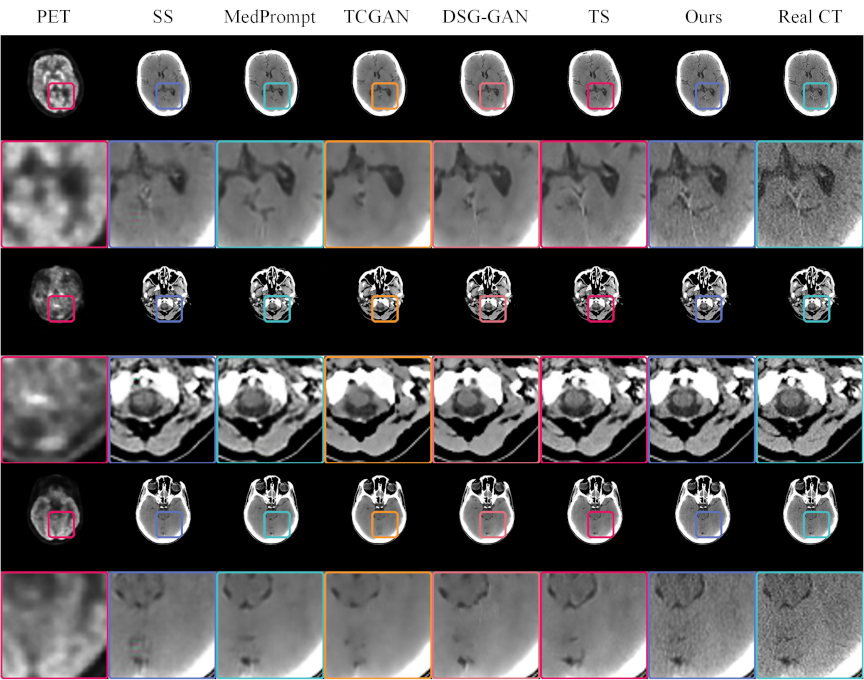

We performed a visual comparison of images generated by different models, as illustrated in Fig. 9. The original PET and real CT images served as references. A single-stage GAN yielded a blurry image with color artifacts, while TCGAN exhibited overly smooth textures, lacking structural detail. MedPrompt introduced spurious vertical shadows, indicating discrepancies from the real CT. By contrast, DSG-GAN captured certain subtle brain features, although the overall texture remained less consistent than desired.

Fig. 9. CT images generated by various models, compared with real PET and CT images. The odd rows present the complete paired PET–CT images, while the even rows provide magnified views of specific regions within these pairs. Each model uses the PET image located at the extreme left as the input. The real CT images positioned at the extreme right serve as references for comparison. This format allows for a detailed evaluation of the ability of each model to replicate the structural and textural details found in real CT scans, facilitating a direct assessment of their performance in medical imaging applications.

Notably, the triple-stage network attained superior global texture fidelity, despite missing some localized details. Integrating a brightness-sensitive loss function further refined texture reproduction, as evident in magnified views like rows 2, 4, and 6, demonstrating closer alignment with real CT images. These findings underscore the effectiveness of a cascading multistage GAN architecture for cross-modal medical image generation, suggesting potential for early disease screening applications.